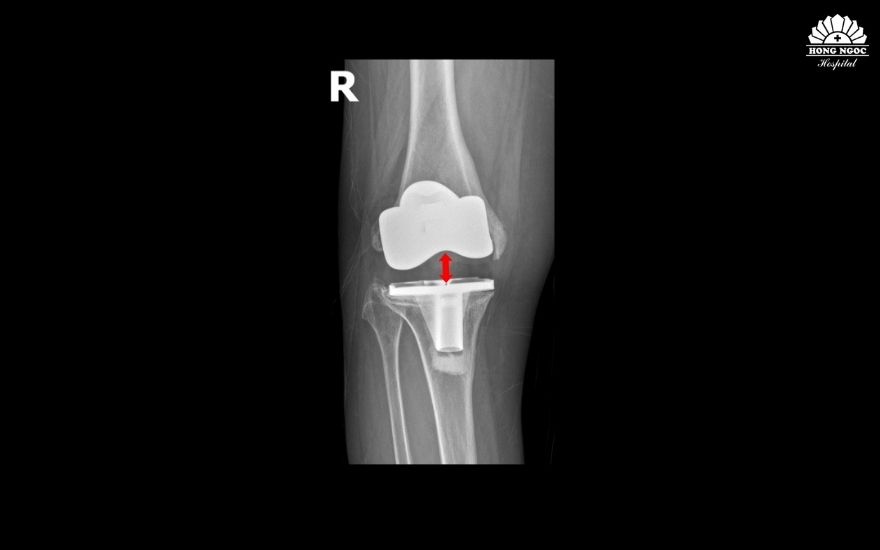

Theo TS.BS Lê Quang Huy, Trưởng khoa Ngoại Chấn thương chỉnh hình - Thần kinh sọ não, BVĐK Hồng Ngọc - Phúc Trường Minh: “Trường hợp của bệnh nhân Oanh hiếm gặp. Chỉ sau gần 5 năm phẫu thuật, cấu phần lồi cầu đùi nhân tạo (phần kim loại bao bọc đầu dưới xương đùi) đã lún vào lồi cầu trong xương đùi ~ 2cm, khiến khớp gối lệch khỏi vị trí ban đầu, mất vững kèm mất cân bằng mô mềm quanh khớp dẫn đến bệnh nhân không đi lại được. Các nguyên nhân gây biến chứng như nhiễm trùng hay viêm xương tuỷ đã được chúng tôi loại trừ, có thể do cơ địa bệnh nhân không phù hợp với loại khớp cấy ghép, tình trạng loãng xương nặng gây tiêu xương hoặc kỹ thuật cắt xương chưa thực sự chuẩn xác. Giải pháp duy nhất để phục hồi vận động và ngăn ngừa nguy cơ tàn phế là phẫu thuật thay lại khớp gối”.

Ca mổ của bà Oanh được đánh giá là phức tạp do gân cơ, dây chằng và cấu trúc xương quanh khớp tổn hại nghiêm trọng, đòi hỏi bác sĩ tính toán kỹ lưỡng để vừa khôi phục trục chân nguyên bản, vừa bảo tồn tối đa gân cơ, hạn chế biến chứng tái phát. Sau khi hội chẩn cùng GS. Hiranaka Takafumi (Giám đốc Trung tâm Phẫu thuật Khớp, Bệnh viện Takatsuki, Nhật Bản), TS.BS Lê Quang Huy quyết định loại bỏ khớp nhân tạo cũ, thay thế khớp mới bằng kỹ thuật thay khớp gối gióng trục động học, không cắt gân cơ với đường mổ nhỏ, ít xâm lấn, giúp bệnh nhân ít đau, có thể đi lại sau 1-2 ngày. Ngoài ra, bác sĩ sử dụng khớp bản lề chuôi dài để tăng độ vững, khôi phục trục chân, giúp người bệnh khôi phục chức năng và tầm vận động, hạn chế nguy cơ di lệch khớp.

Sau 2 giờ, ca mổ diễn ra thuận lợi. Khớp gối mới vừa vặn với ổ khớp, trục chân nguyên bản được khôi phục. Bà Oanh chia sẻ: “Lần mổ này nhẹ nhàng hơn lần mổ trước của tôi, lần trước, hơn 10 ngày tôi vẫn đau, không đi lại được. Lần mổ này, sau 2 ngày tôi đã vận động nhẹ nhàng, ngày thứ 5 tôi đã đi bỏ khung, tự chủ trong sinh hoạt cá nhân rồi. Tôi và gia đình đều bất ngờ bởi chỉ sau 1 cuộc phẫu thuật, tôi đã có thể đi lại được bình thường. Tôi xin gửi lời cảm ơn tới BS Huy cũng như tập thể nhân viên bệnh viện đã chăm sóc cho tôi rất chu đáo, tận tình.”